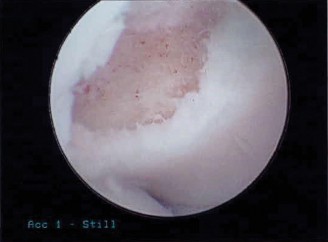

You send the patient for an MRI, which is shown in Figure 2–66.

Figure 2–66

Based on the clinical examination and imaging, what is the most likely etiology of the patient’s symptoms?

- Suprascapular nerve entrapment at the spinoglenoid notch by a paralabral cyst

The correct answer is (C). The patient’s clinical examination findings of isolated

weakness in external rotation and atrophy of the infraspinatus muscle point to suprascapular nerve entrapment at a location past the exit point for the branch to the supraspinatus muscle. Also, MRI reveals a posterior labral tear with a paralabral cyst that is compressing the suprascapular nerve at the spinoglenoid notch. Choice A, while fitting with the patient’s clinical examination, does not fit with the MRI showing paralabral cyst. Choices B and D are incorrect because entrapment of the suprascapular nerve at the suprascapular notch by scapular body fracture or by the transverse scapular ligament (more common) would lead to weakness/atrophy in both supraspinatus and infraspinatus muscles as the suprascapular notch is proximal to the nerve branch point to the supraspinatus muscle.